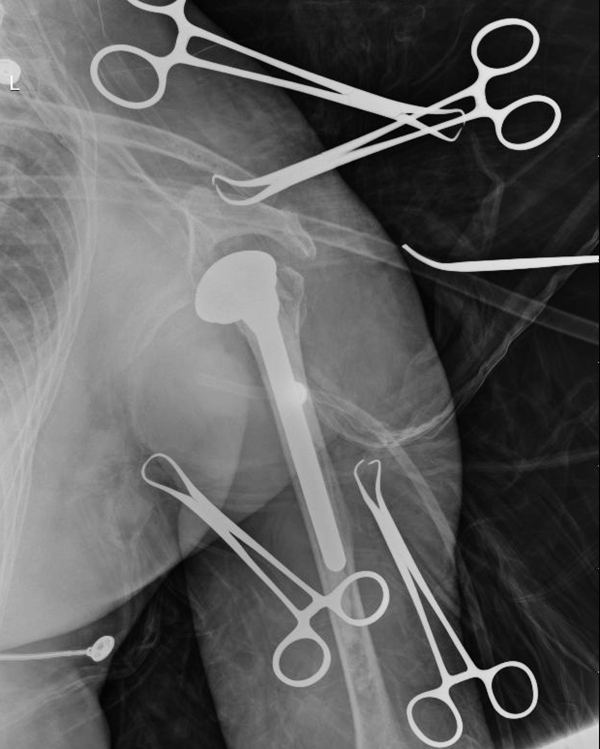

4月30日,骨四肢二区丰哲教授带领手术组成功为黄姓老人进行了人工肩关节置换术,手术顺利,术中X片显示,手术成功。术后第二天患者即可开始早期的功能锻炼。

术中X片